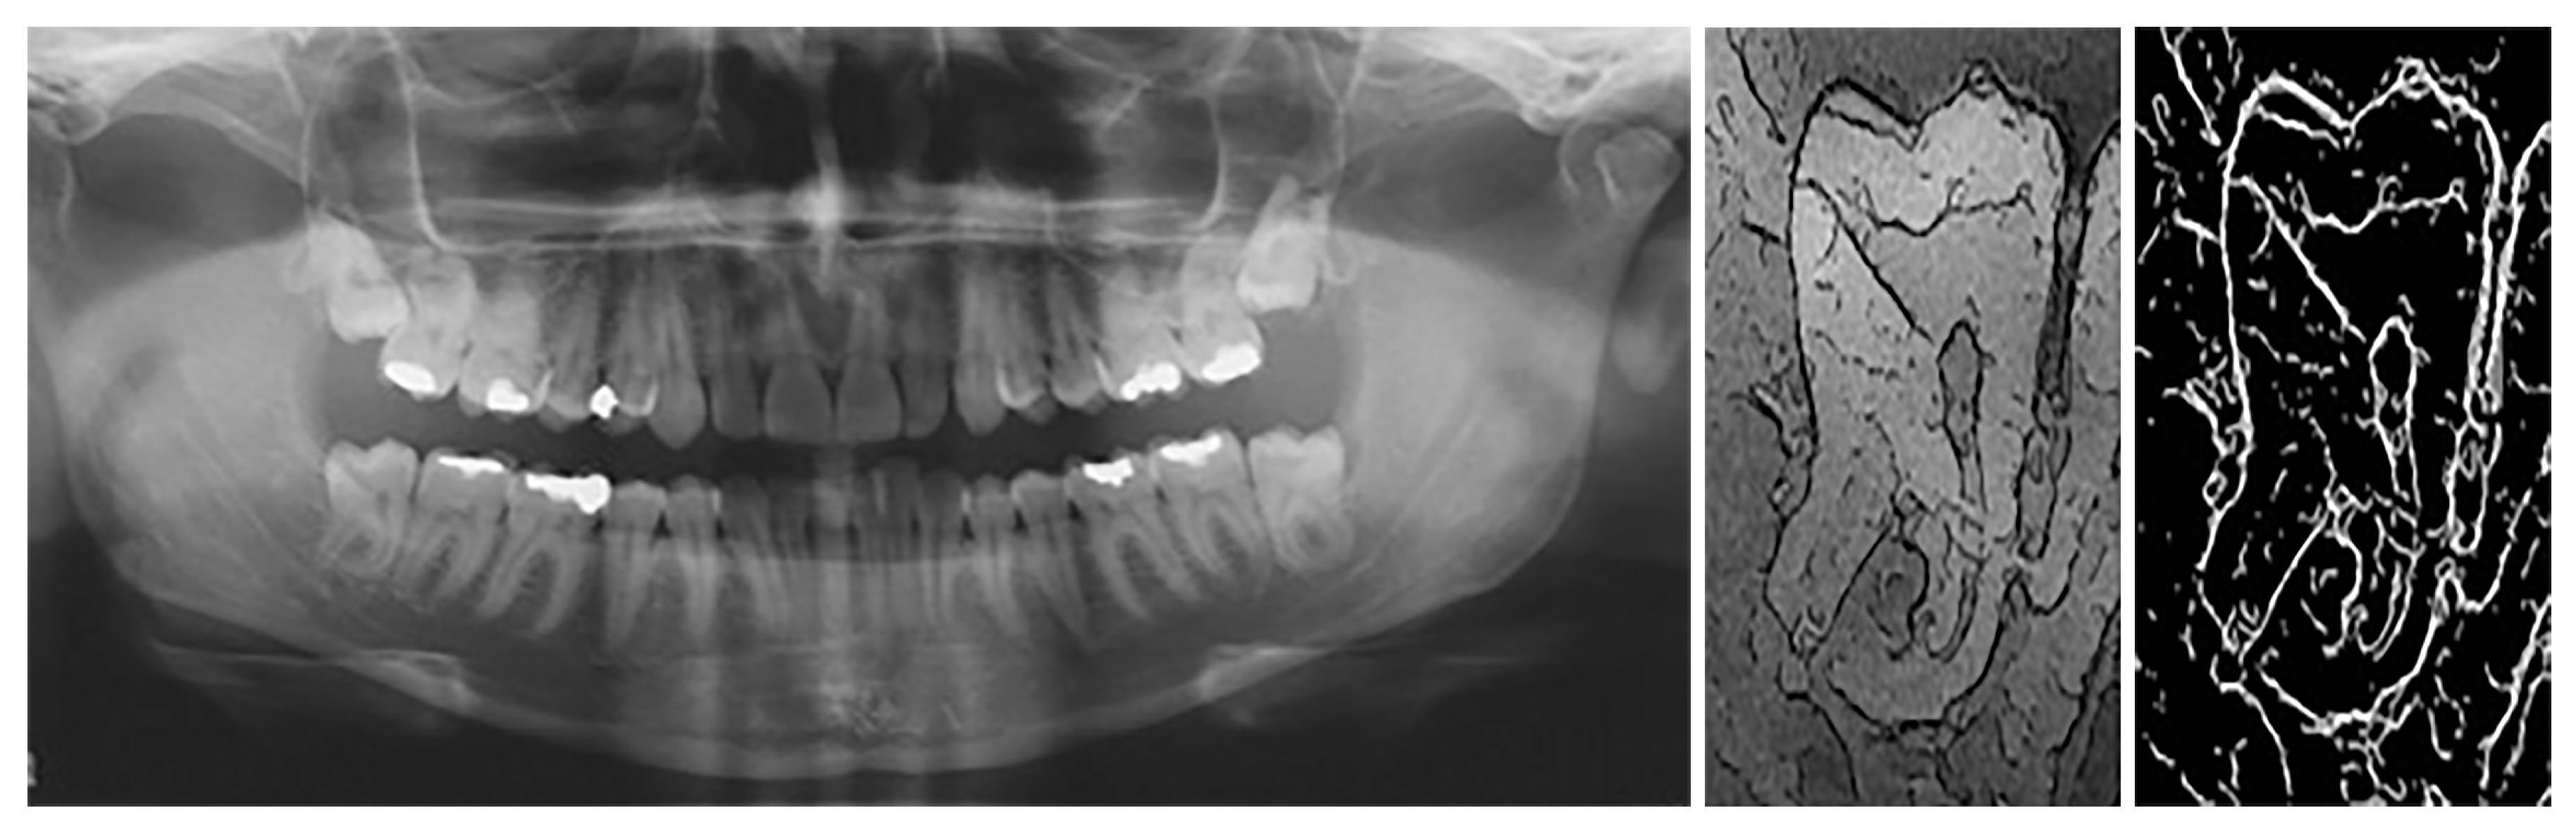

- Gráfová, L.; Kašparová, M.; Kakawand, S.; Procházka, A.; Dostálová, T. Study of edge detection task in dental panoramic X-ray images. Dentomaxillofac. Radiol. 2013, 42, 20120391. [Google Scholar] [CrossRef] [PubMed]